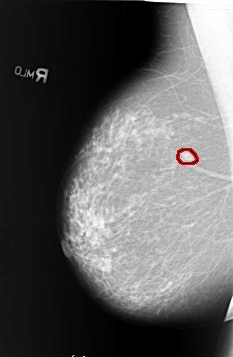

B_3405_1.RIGHT_MLO

FILE: B_3405_1.RIGHT_MLO.OVERLAY

TOTAL_ABNORMALITIES 1

ABNORMALITY 1

LESION_TYPE MASS SHAPE OVAL MARGINS SPICULATED

ASSESSMENT 5

SUBTLETY 4

PATHOLOGY MALIGNANT

TOTAL_OUTLINES 1

BOUNDARY